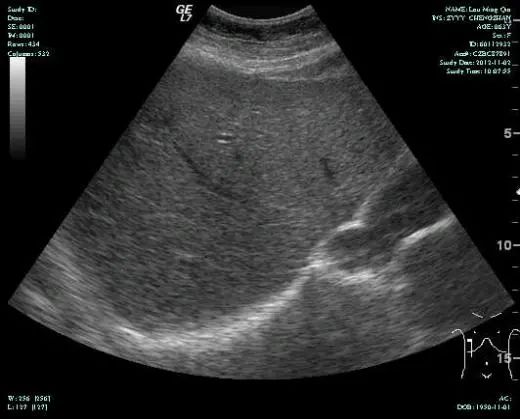

CT-T

CT-H1

MR-H1

影像学检查结果评估:cPD。